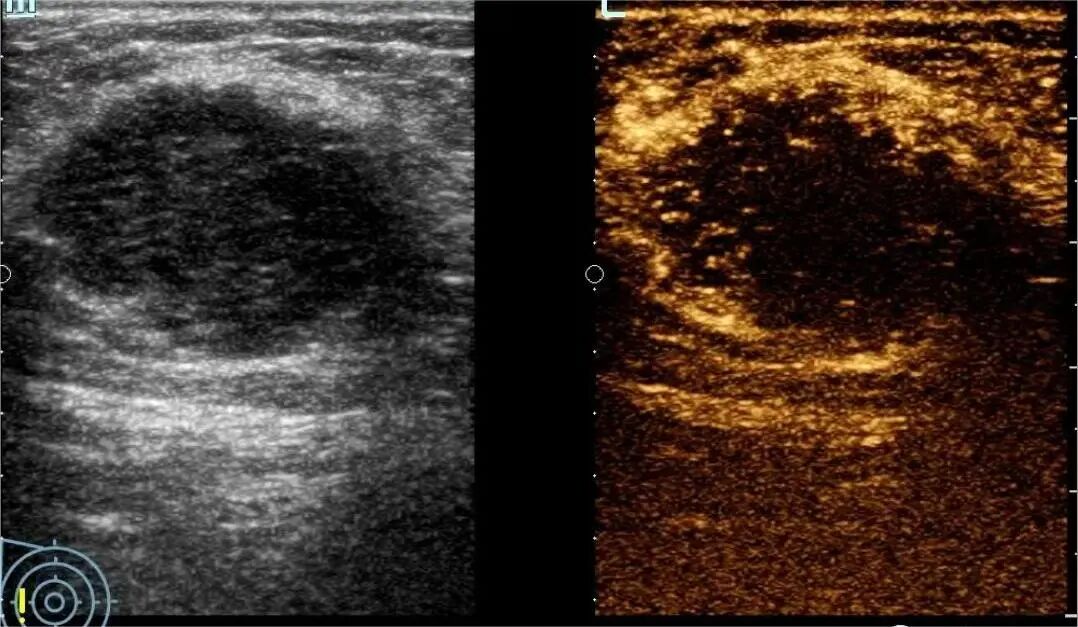

1月7日,贵州航天医院第91次晨读会由我院超声科医师杨向蓉作学术交流,她以“小微泡,大作用——右心声学造影”为题,详细讲解了右心声学造影的基本原理、适用情况、操作方式及心脏异常分流评估特点等内容,涵盖了该技术的实施条件、所用造影剂类型及多种激发试验方法,并通过多个病例图文资料分享了右心声学造影在相关症状病因探寻中的辅助角色,为临床评估提供了一种观察途径,有助于从循环角度了解某些症状的可能原因,在相应症状的病因分析中具有一定的参考意义。 贵州航天医院 超声科专家简介 吴艳辉 中共党员,超声科学科带头人,主任医师 专业擅长:从事超声诊断工作30余年,对心血管、小器官超声、超声引导下介入等具有丰富的临床经验。 胡大海 超声科主任,副主任医师 专业擅长:从事超声工作20余年,对心血管、外周血管、浅表器官、成人颅脑、超声造影诊断及超声引导下介入等具有丰富的临床经验。 骆科美 中共党员,超声科副主任医师 专业擅长:从事超声诊断工作30余年,对胎儿心脏及颅脑、妇产超声诊断、盆底超声等具有丰富的临床经验。 刘 敏 超声科副主任医师 专业擅长:从事超声诊断工作20余年,对妇产科超声、心脏血管超声诊断具有丰富的临床经验。 韩锡铁 超声科副主任医师 专业擅长:从事超声诊断近20年,对心血管、外周血管、浅表器官、肌骨神经超声诊断具有丰富的临床经验。 杨向蓉 中共党员,超声科主治医师 专业擅长:从事超声诊断工作16年,擅长心血管、浅表器官、盆底、腹直肌超声、右心声学造影及超声引导介入等技术。 贵州航天医院超声科简介 基本情况 贵州航天医院超声科配备多种超声检查设备(飞利浦彩超(IU-22、IU-Elite、EPIQ5、EPIQ7),迈瑞彩色超声(ResonaI9T、RechoR9、Resona I9、DC-8)、GE-VolusonE8、汕头SIUIAPogee6800、床旁彩色超声诊断仪等),设有心血管诊室、外周血管诊室、妇产科诊室、腹部诊室、绿色通道、浅表小器官等检查室。 诊疗范围 科室业务覆盖腹部、泌尿、妇科、产科(常规、NT筛查、系统筛查及高危妊娠监护)、成人心脏、外周血管、浅表器官(包含甲状腺、乳腺、阴囊、眼睛等)、颅脑(小儿颅脑、成人帕金森辅助筛查)、小儿肺超、超声造影、盆底、腹直肌、肌骨神经等检查及各种超声介入引导。 专科特色 四肢血管超声检查、产前系统筛查及超声监护、超声造影检查技术、介入超声临床应用、经颅脑实质超声辅助筛查诊断帕金森病、小儿髋关节筛查、女性性早熟超声诊断、盆底、腹直肌超声检查等。 NT超声检查 超声介入引导 肝脏超声造影 甲状腺造影 颅脑超声帕金森辅助检查 乳腺超声造影 上肢动静脉造瘘超声检查 双胎超声筛查 下肢血管超声检查 右心造影 end